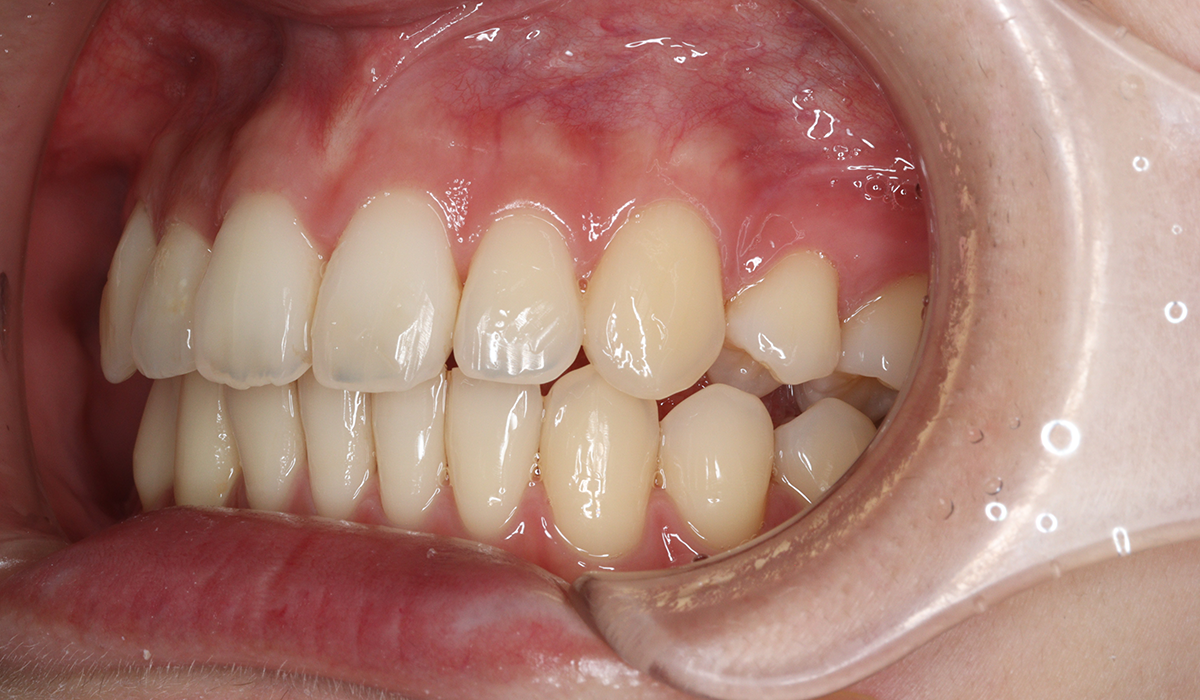

左側

BK終了時